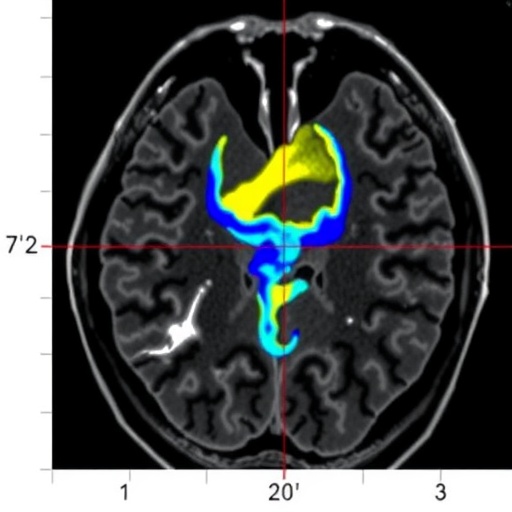

Mitral annular disjunction is often subtle and can easily be overlooked in clinical practice. The implications of this condition extend far beyond structural abnormalities; it has serious repercussions for the heart’s functionality and rhythm. The innovative use of cardiac magnetic resonance imaging (CMR) allows for a detailed investigation of this anomaly, providing insights that conventional imaging modalities might miss. The research team’s approach incorporates T1 mapping and feature-tracking strain analysis to enhance the understanding of MAD’s physiological impact in the pediatric demographic.

The study focused on a cohort of children diagnosed with various heart conditions, all of whom underwent thorough evaluations using state-of-the-art CMR techniques. The incorporation of T1 mapping is particularly notable, as it enables the quantitative assessment of myocardial tissue properties. By analyzing T1 values, the researchers can gain insights into aspects such as myocardial fibrosis and edema, both of which are critical in understanding the implications of MAD.

Feature-tracking strain analysis, another cornerstone of this research, provides an additional layer of detail by evaluating myocardial deformation. This technique allows for the quantification of global and regional strain, revealing how well the heart is functioning under various conditions. By combining these advanced imaging techniques, the study presents a robust method for assessing the relationship between MAD and cardiac mechanics, offering potential avenues for intervention.